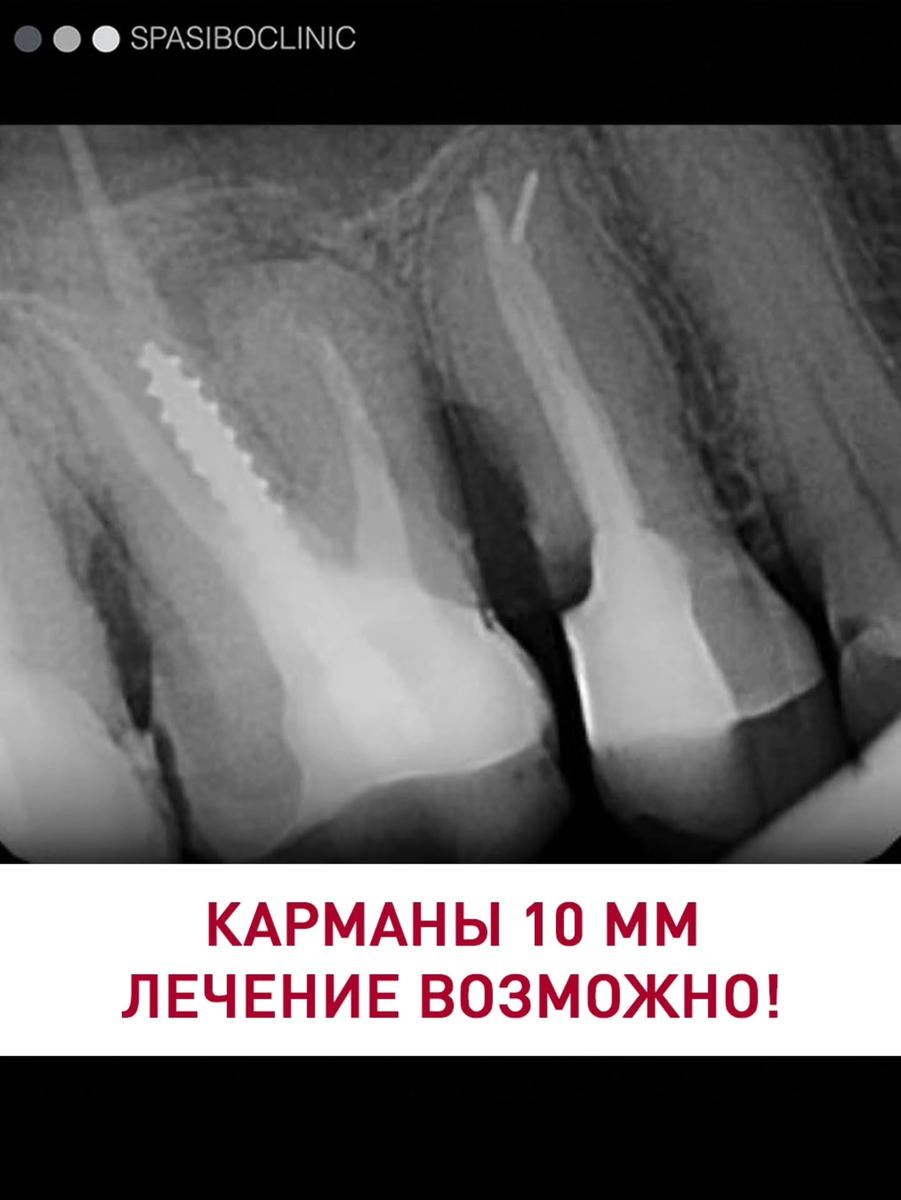

КАРМАНЫ 10 ММ ЛЕЧЕНИЕ ВОЗМОЖНО!

Глубокие десневые карманы можно вылечить без операции🔬

Растяжение тканей позволяет работать на глубине до 10 мм без повреждения десны.

А бионические коронки разработаны специально для пациентов с пародонтитом. Их можно устанавливать максимально глубоко под десну, и десна прилегает к ним настолько плотно, что бактерии не проникают внутрь.

На фото — полная реабилитация пациента с тяжёлой формой пародонтита. Результаты двухлетнего наблюдения⬆️